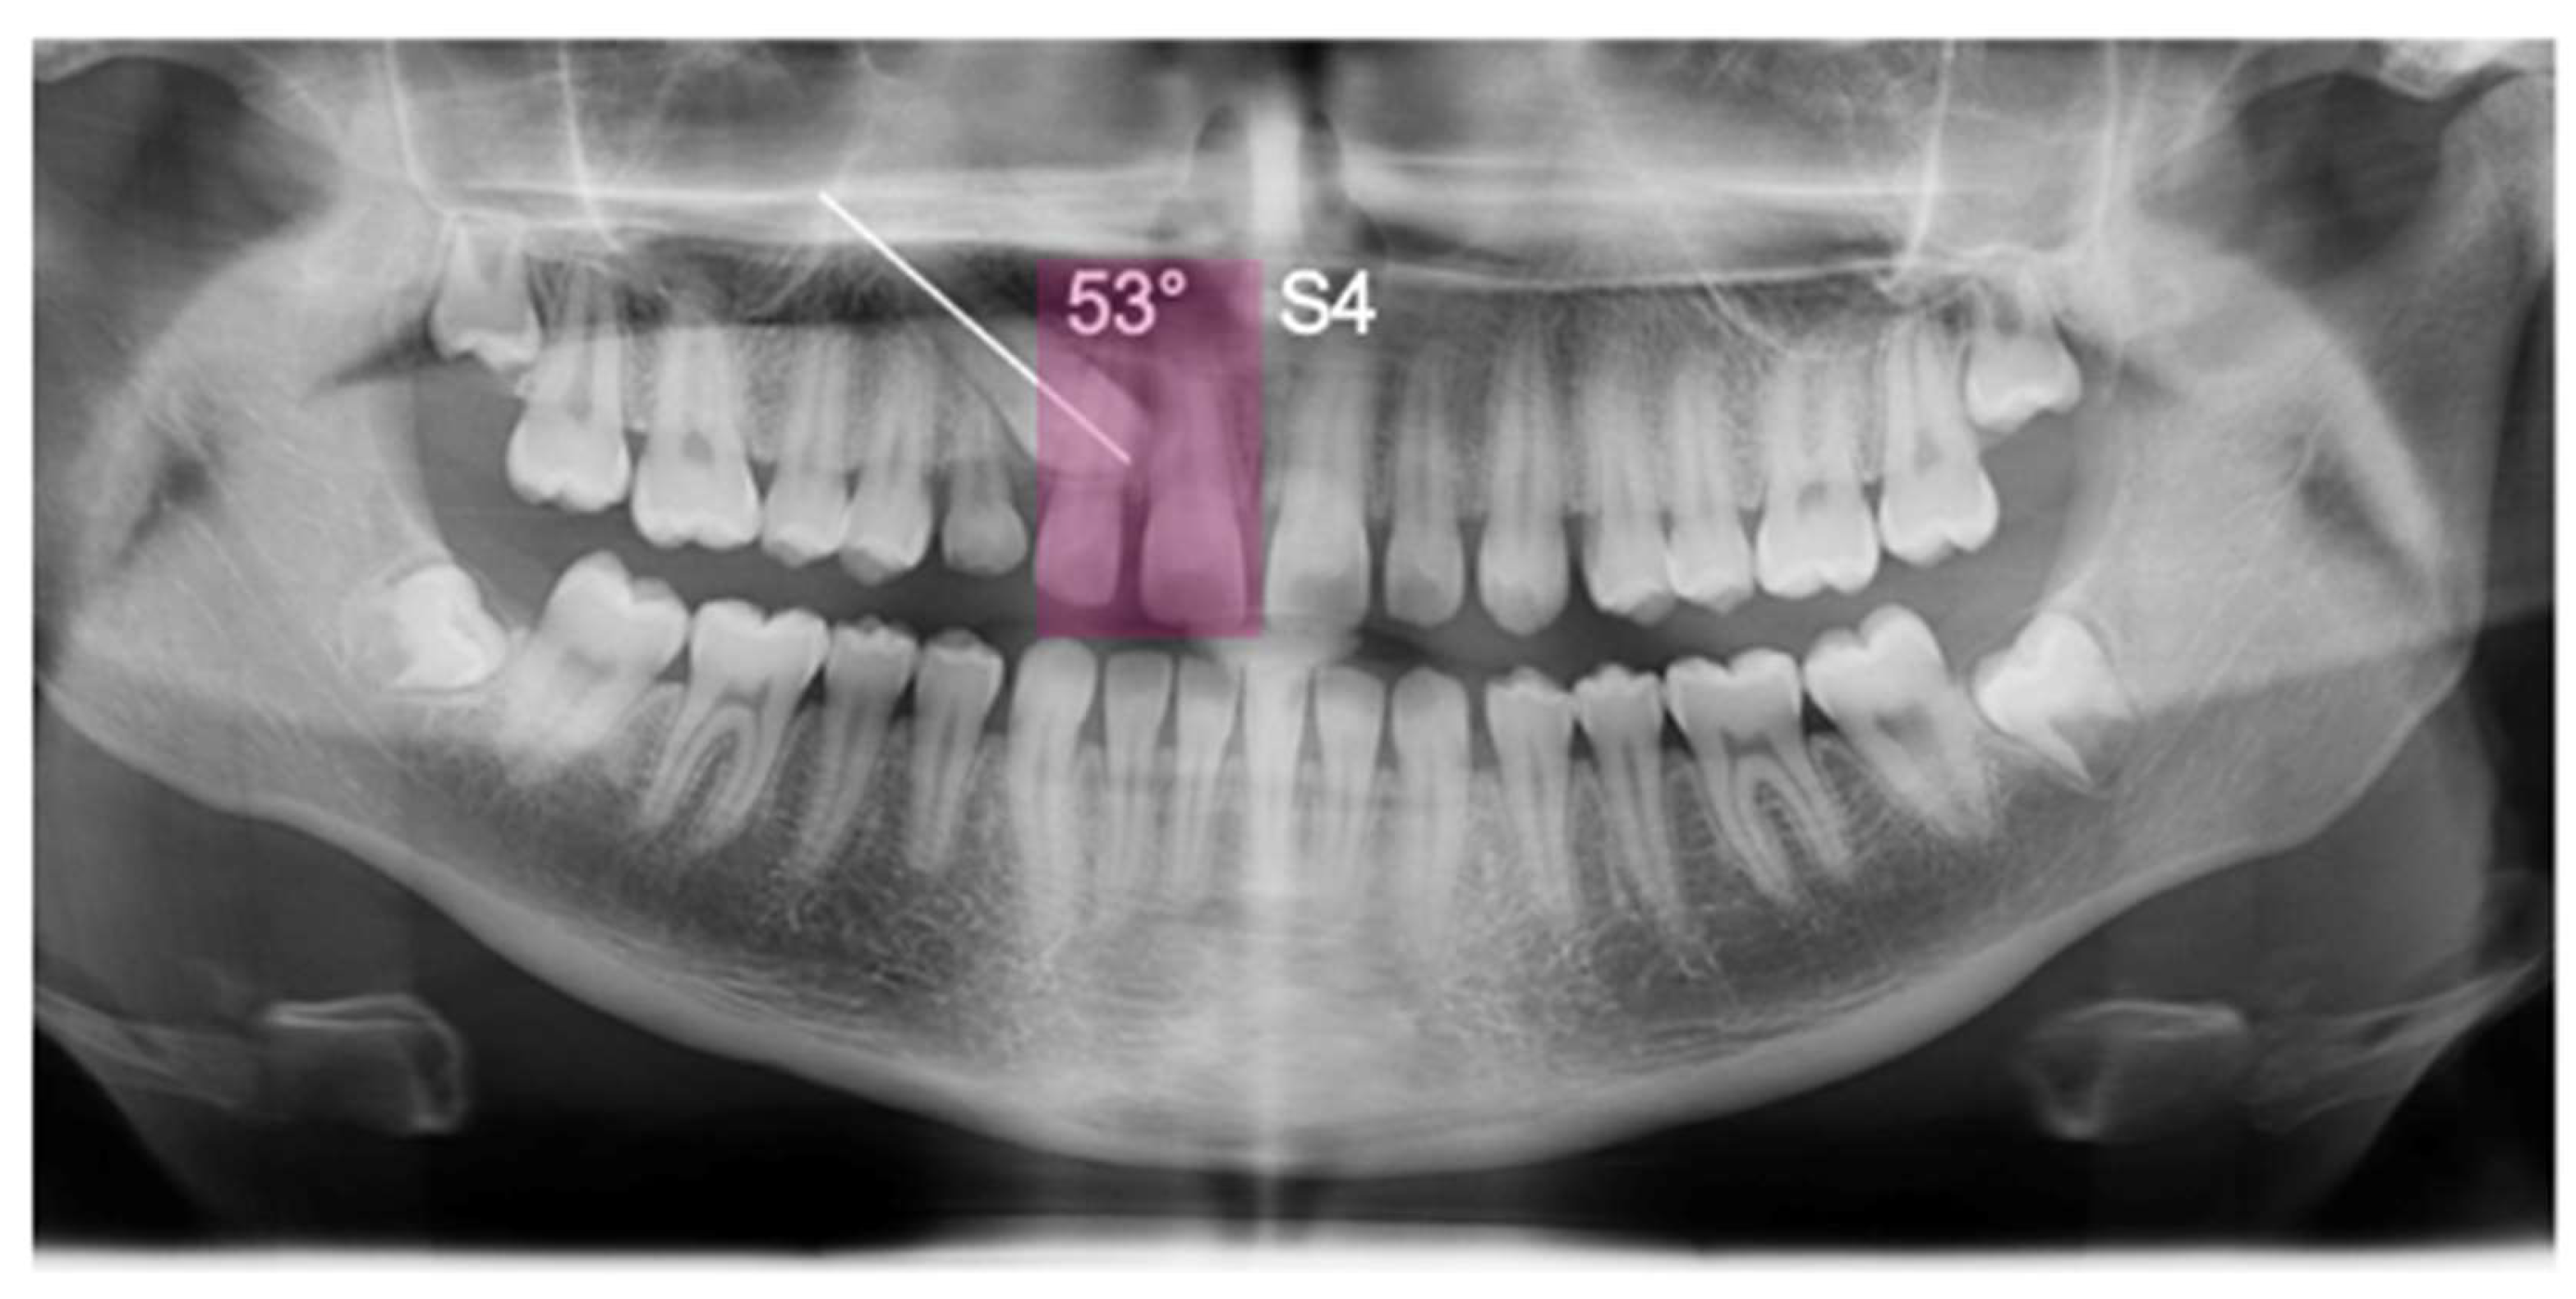

The panoramic X-ray showed unilateral permanent canine displacement in sector four with an alpha angle of more than 53° degrees according to the Ericson and Kurol classification (Figure 2).

Figure 2.

Pre-treatment panoramic X-ray with the evaluation of alpha angle and sector according to the Ericson and Kurol classification.